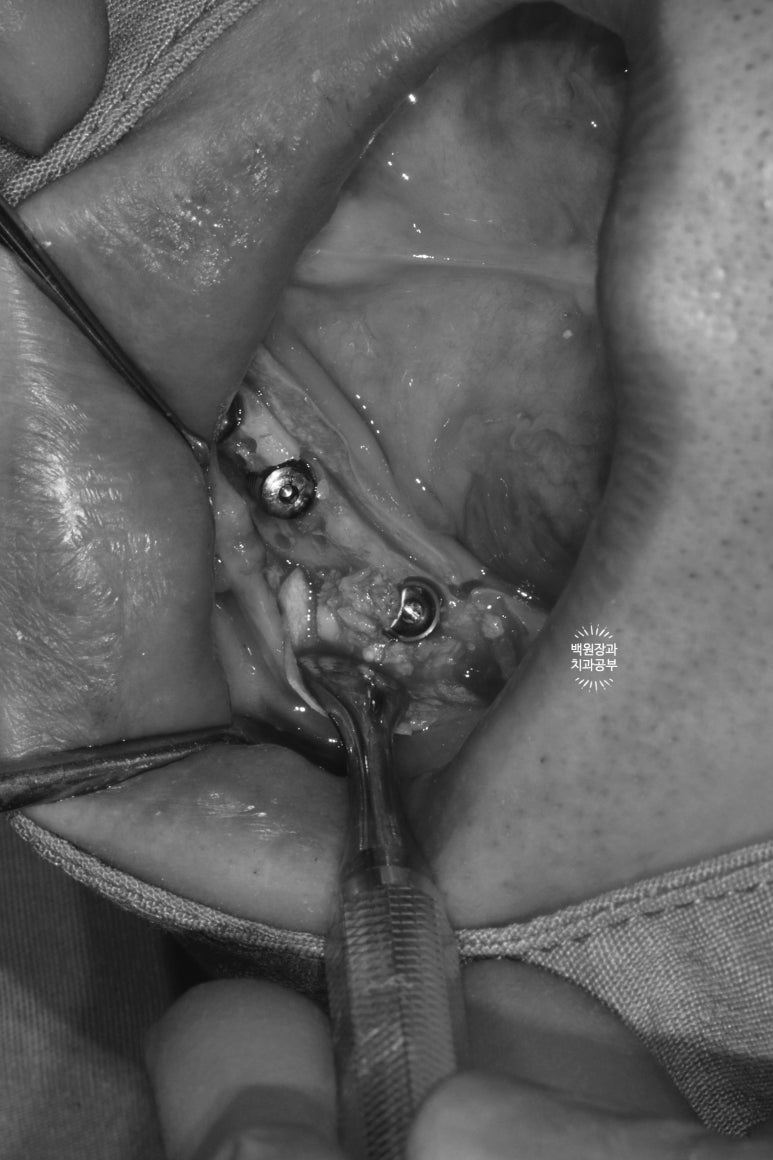

가장 먼저 잇몸뼈의 두께를 확인해야합니다.

CT가 틀릴리 없습니다... 상당히 얇은 잇몸뼈를 관찰할 수 있습니다.

왼쪽 위 잇몸뼈가 상당히 얇음을 역시나 확인할 수 있었습니다.

폭이 약 2-3mm 정도로.. 직경 3.5mm 임플란트를 심을 수 없을 것만 같은 곳이었죠.

이론적으로 3.5mm 임플란트를 심으려면 약 7.5mm 폭의 잇몸뼈를 만들어내야하니 참 곤란한 상황입니다.

오른쪽 위는 그래도 조금 나았던 것으로 기억...

상악동 뼈이식술도 넉넉히 많이 해드려야 했기 때문에, 앞서 언급했던 것처럼 충분한 잇몸 거상이 필요한 상태였습니다. 좋은 시야는 좋은 수술 결과를 만들어내는데 큰 도움을 줍니다.

잇몸뼈가 너무 얇다보니, 임플란트를 위치시키면 이렇게 임플란트의 일부가 드러날 수 밖에 없었고, 이제 어렵디 어려운 잇몸뼈이식이 기다리고 있는 상황..